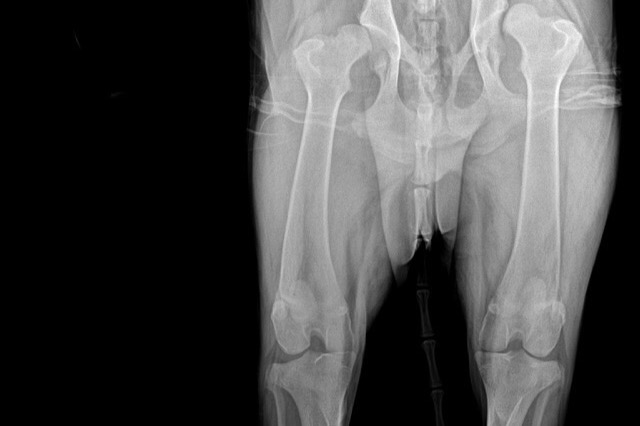

As all puppies do, Chico grew rapidly, and we realized that his hind legs weren't growing with the rest of his body and were extremely under-developed.  After a visit to the vet, we learned that he had a severe case of hip dysplasia. We quickly got him on supplements, medications, and an at-home physical therapy regimen to help with the pain but since he's still a growing pup, these remedies proved no results.

Over the past few weeks, Chico's condition has worsened. He can't run or walk without bunny hopping his hind legs, and needs assistance laying down and getting up. Since our last vet visit with Chico, we learned that the only option for Chico at this point is surgery. He needs a femoral head ostectomy which is a surgical operation to remove the head and neck from the femur. It is performed to alleviate pain, and is a salvage procedure, reserved for condition where pain can not be alleviated in any other way. Chico will need two of these procedures, one for each hip, which will cost $2,500 each.